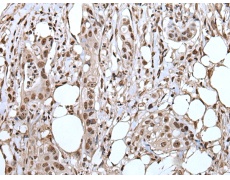

IHC positive control: |

Human colorectal cancer and human cervical cancer |